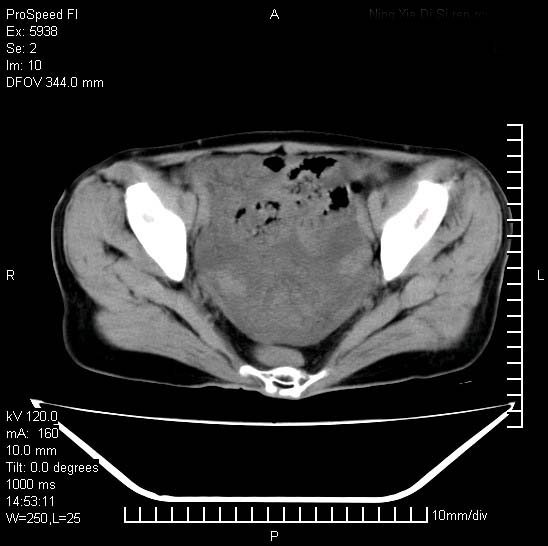

反复小腹疼痛,盆腔积液3年,无发热,曾抗痨一段时间。

右下腹肠管壁增厚,边缘有侵润改变及点状低密度影,内侧可见局限性肿块。考虑-----淋巴瘤或增生型肠结核----盆腔积液-----建议肠镜检查

考虑盆腔及右下腹感染性病变(结核可能)。

结核性腹膜炎伴积液。右侧髂骨骨窗看看,是否有骨质破坏。

提示结核性腹膜炎合并盆腔积液。建议查ppd或tb抗体。

考虑右下腹及盆腔感染性病变(结核?)。